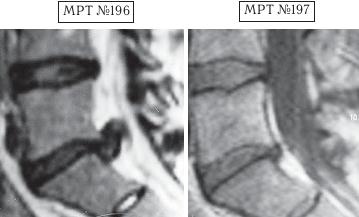

Пример № 3.

На МРТ № 196 наблюдается состояние поясничного отдела позвоночника после операций: рецидив грыжи межпозвонкового диска в сегменте LV—SI с формированием секвестра с миграцией в краниальном направлении, абсолютный стеноз спинномозгового канала.

На МРТ №s197 — состояние поясничного отдела позвоночника после лечения методом вертеброревитологии.